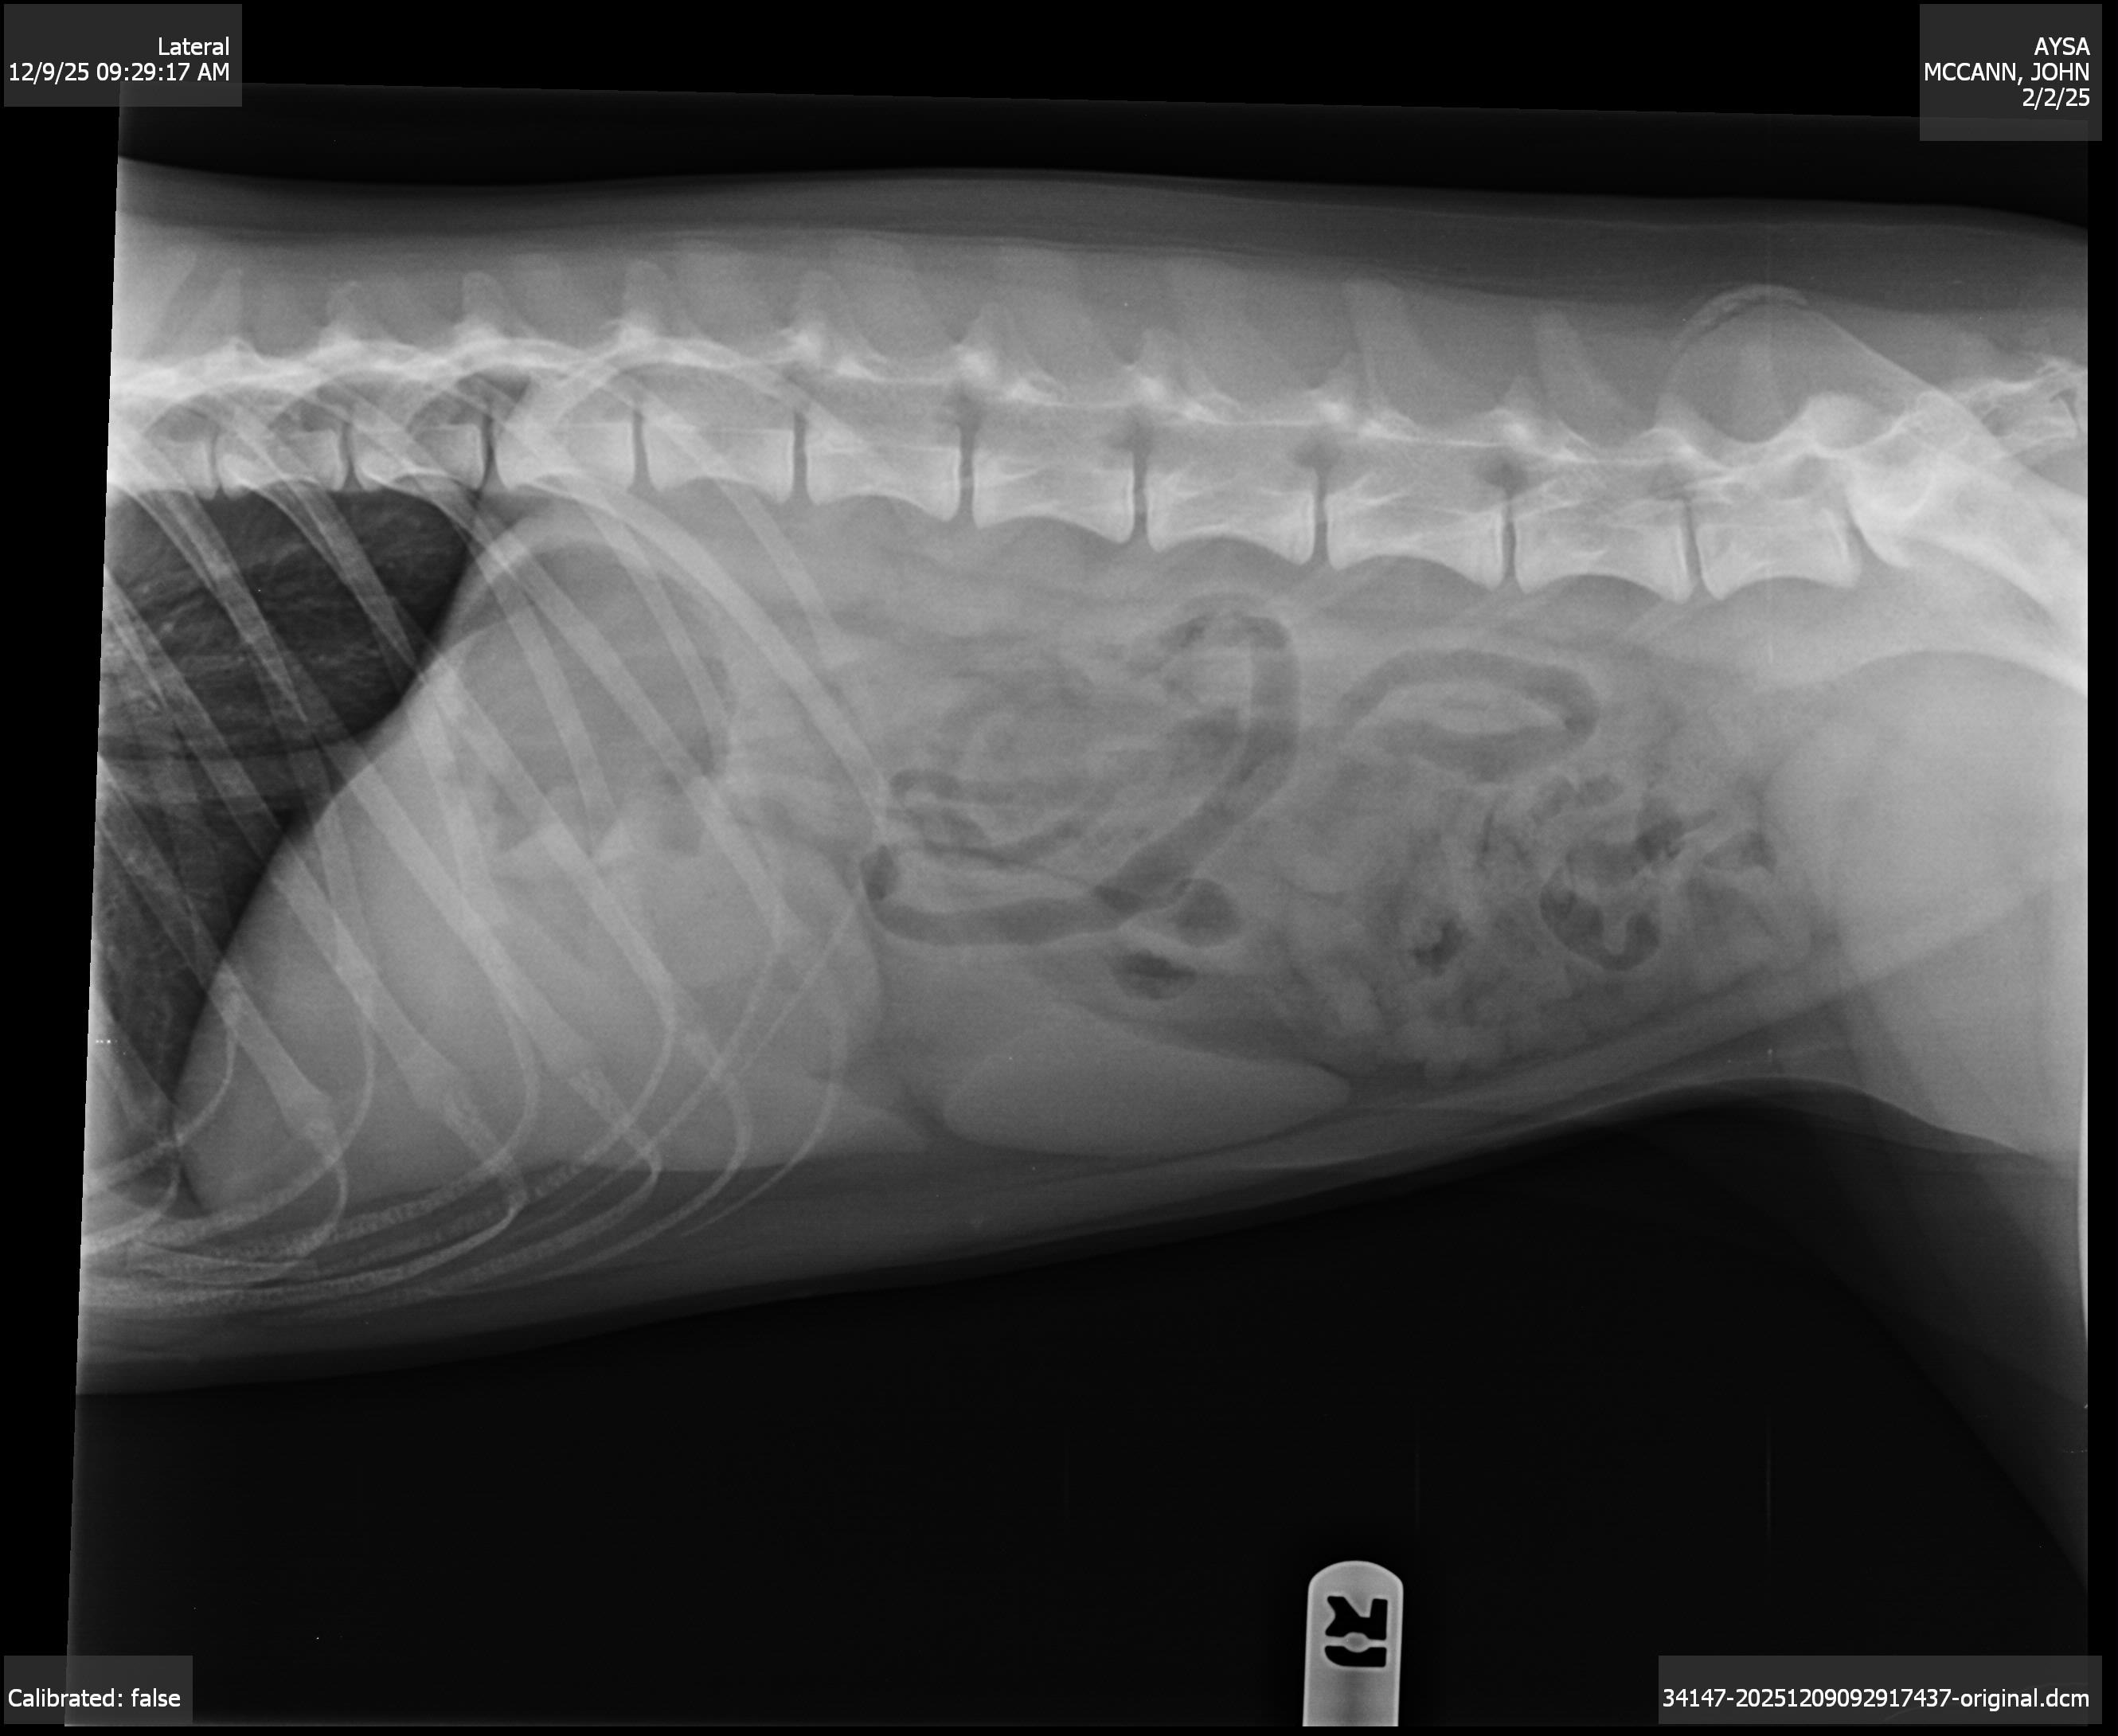

She finally got into the vet and went into emergency surgery around 2 PM today. The vet originally thought she had swallowed a toy, but once they opened her up, they discovered something much worse, severe chronic stomach ulcers and extremely thickened, inflamed stomach tissue that looked like a mass. These ulcers were bleeding into her stomach and causing her to vomit blood. Her gums were pale, and she could barely stand without help.

During surgery, she also began bleeding from her nose. The vet is now concerned she developed aspiration pneumonia from all the nonstop vomiting. Because of everything going on, Aysa has to stay in the hospital for at least two nights on IV fluids and medications. She’s far too sick to come home right now.